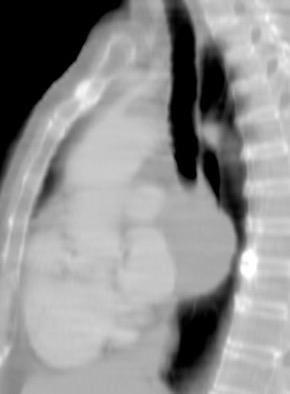

6. ÁREAS DEL MEDIASTINO EN TC